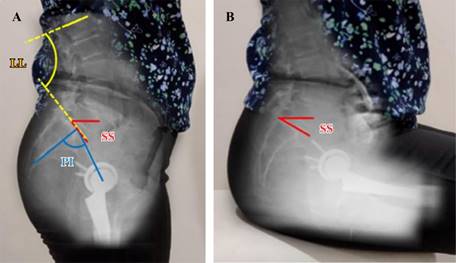

En la radiografía lateral en bipedestación, se midió la incidencia pélvica (PI) (Figura 1), la lordosis lumbar (LL), la inclinación del sacro (sacral slope, SS), el plano pélvico anterior (APP) y el ángulo pélvico femoral (PFA). Mientras que, en la radiografía lateral en sedestación, se midió la inclinación del sacro (SS) y el ángulo pélvico femoral (PFA) (Figura 2).

Figura 1: A) Posición de la pelvis en bipedestación analizando el APP (verde), LL (amarillo), PI (azul) y SS (rojo). B) Posición de la pelvis en sedestación. En condiciones normales la inclinación posterior de la pelvis aumenta durante la sedestación condicionando una modificación importante en el SS. APP = plano pélvico anterior. LL = lordosis lumbar. PI = incidencia pélvica. SS = inclinación sacra.